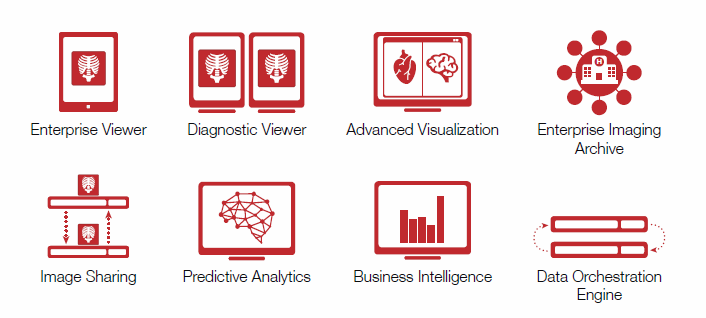

Vital Images has reconciled its vision of the distant future with near term reality. The company has come up with an ...